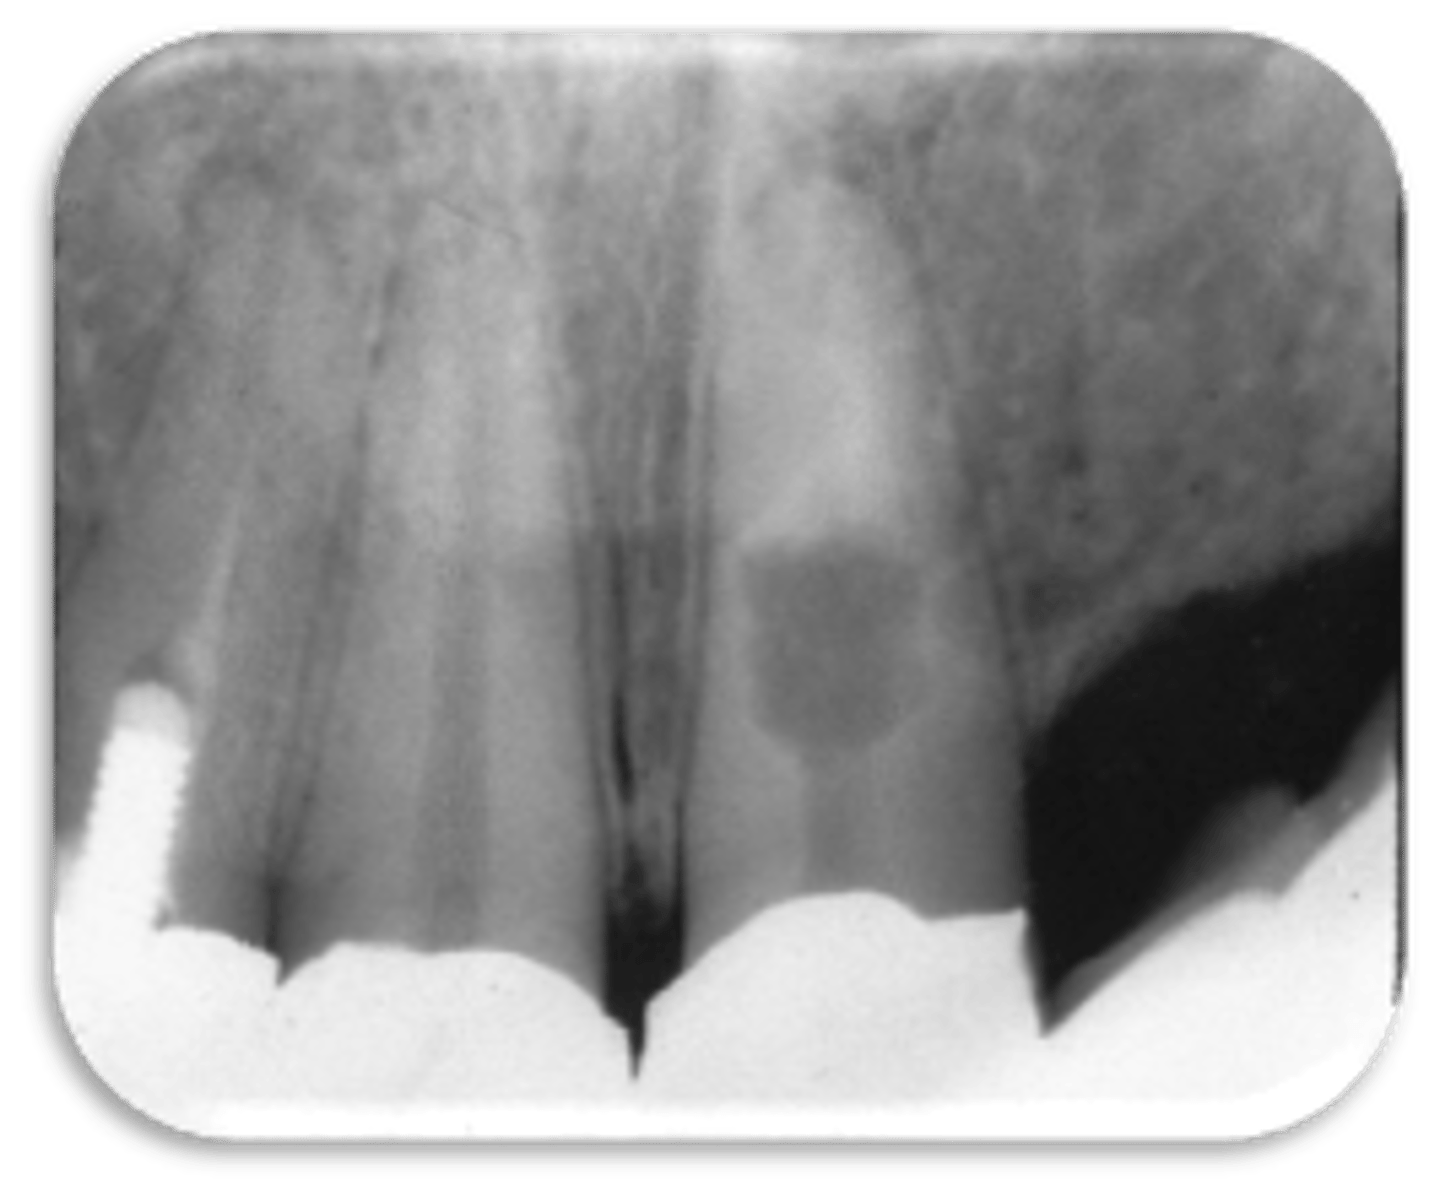

vertical root fracture

ID the problem:

- May not show on PA radiographs

Presents with signs of:

- J-shaped lesion/lateral radiolucency

- Isolated deep pocket

- Coronally located swelling or sinus tract